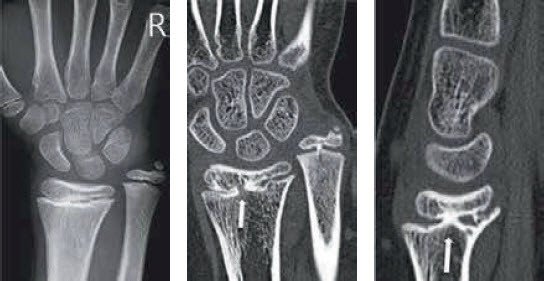

knöcherne Fugenbrücke

Im Röntgen und CT zeigt sich die knöcherne Fugenbrücke (Pfeil)

Der Verdacht auf eine Fugenbrücke ergibt sich meist aufgrund des Nativröntgenbefunds – häufig fällt dann bereits eine sekundäre, gelenknahe Achsenfehlstellung des Knochens oder ein vermindertes Längenwachstum auf. Die Diagnose kann anhand einer MRI-Untersuchung bestätigt werden; die beste Grössen- und Lagebestimmung ermöglicht aber eine CT-Darstellung.